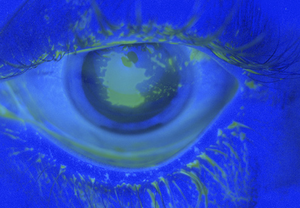

- Fluorescein Exam

- Apply 1 gtt of flourescein or utilize strip with anesthetic

- Use Wood's Lamp or Slit Lamp with colbalt blue light

- Fluoresceine will fill corneal defects and glow

- Multiple vertical abrasions suggests foreign body embedded under the upper lid